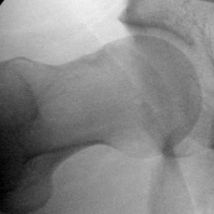

- Femoroacetabular Impingement (FAI) - Cam deformity; Pincer deformity

Hip conditions often improve with conservative treatment including a short course of rest, anti-inflammatory pain medication, and physical therapy. An ultrasound-guided cortisone injection is sometimes necessary for patients with persistent pain. If pain continues despite conservative treatment, hip arthroscopy is an excellent treatment option for patients with labral tears, femoroacetabular impingement (FAI), tears of the gluteus medius or proximal hamstring, among other conditions.

Click on a hip condition below to see the repair.